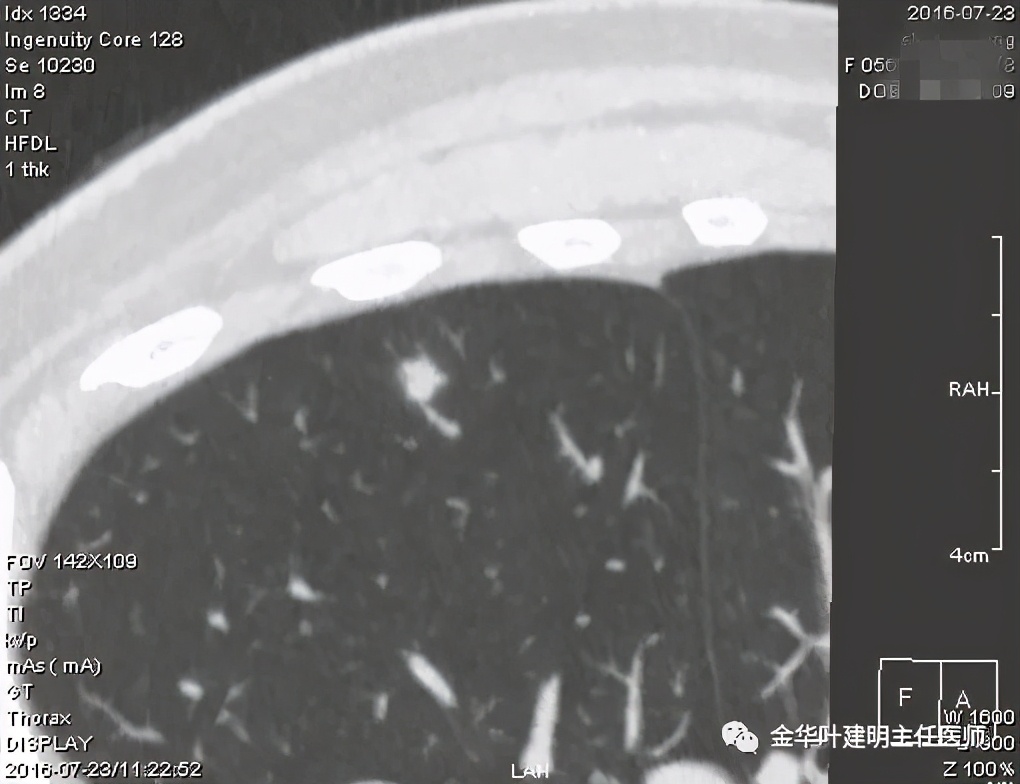

我们来看以往的隐球菌感染是怎样的影像表现:

我们看到它们的共同特征是:实性结节伴有晕征(边缘略糊,看不清的感觉),同时实性的病灶缺乏收缩力(没有胸膜凹陷及毛刺牵拉或纠集感)。